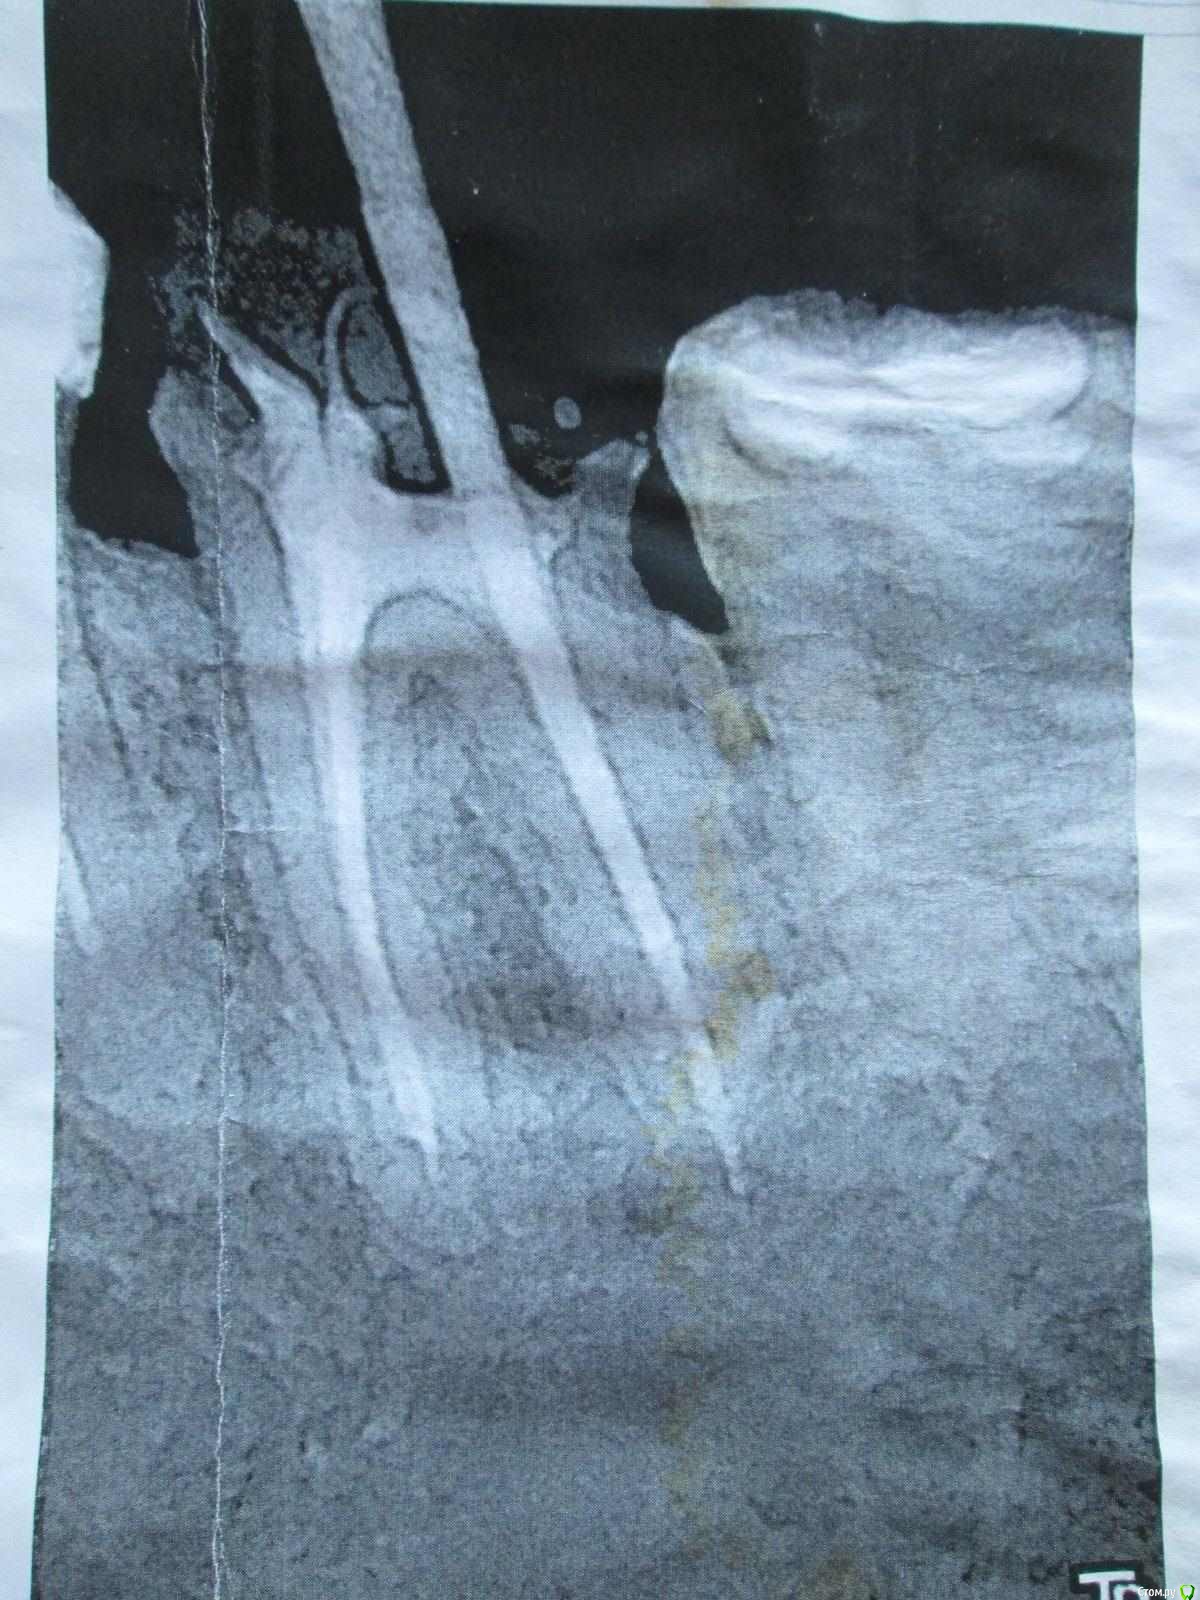

37-й зуб. Депульпирован, стояла большая пломба. В 2013 году  откололась наружная стенка зуба, скол близко к корню. Стоматологом № 1 был поставлен штифт, коронка восстановлена пломбой (фото с торчащим штифтом от 2013 года). Через год наружная часть пломбы откололась прямо по штифту, так ходила три года, ничего не царапало, не мешало. В 2016 году стоматолог № 2 в поликлинике уговорила запломбировать, в результате сделала скошенную наружную часть пломбы. Фото ротовой полости справа от 07.2019 г. прилагаю.

Вопрос: что делать с 37-й зубом? Хирург не хочет удалять, говорит, что можно восстановить пломбой, и боится повредить 36-й. Не знаю, видно ли на снимках, в каком канале стоит штифт и можно ли поставить еще один штифт (второй штифт врач не поставила, насколько я помню, из-за того, что будет дороже и еще что-то там может не выдержать). Без второго штифта пломба, повторяющая анатомическую форму зуба, я считаю, простоит максимум год. С 36-м зубом тоже непонятно что делать, не идет ли там процесс кариеса на корне…

Между корнями что-то черное (на КТ и 2016 года и 05.2019 года). Не хотелось бы покрывать коронкой зуб с гранулемой между корнями. Стоматолог предложил рассверлить пломбу и посмотреть.